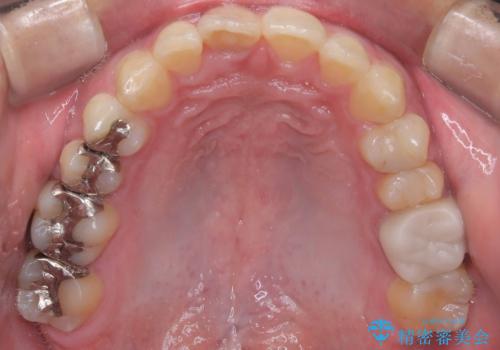

- 「上の前歯の捻じれと下の前歯のでこぼこを治したい」を主訴に来院された患者様です。

矯正検査の結果、非抜歯で矯正可能だったためインビザラインで治療を行いました。

アーチの拡大とIPRで叢生を改善いました。

11ヵ月で矯正を終える事ができ患者様も大変ご満足されていました。